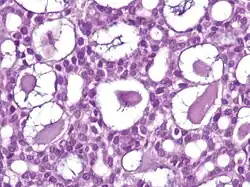

| Type | Histopathology | Other characteristics | Image |

|---|---|---|---|

| Cystic basal-cell carcinoma | Morphologically characterized by dome-shaped, blue-gray cystic nodules.[31]: 647 |

| |